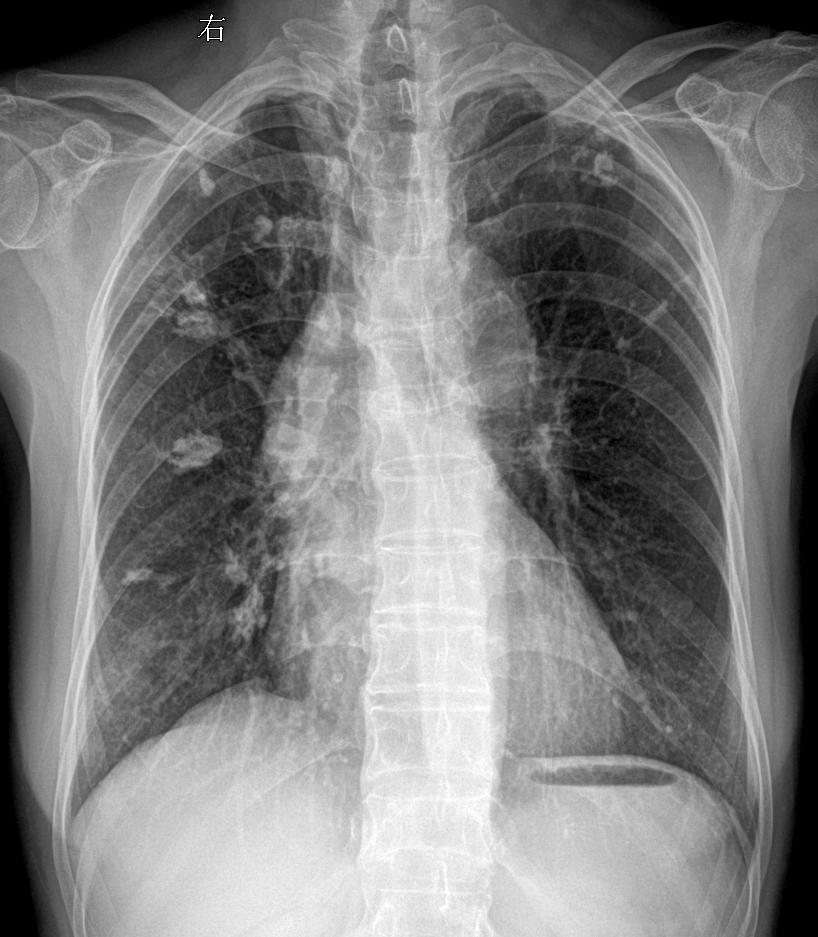

回归工作 双肺可见高密度影钙化灶?陈旧性肺结核?主诉:女 68y 胸闷...